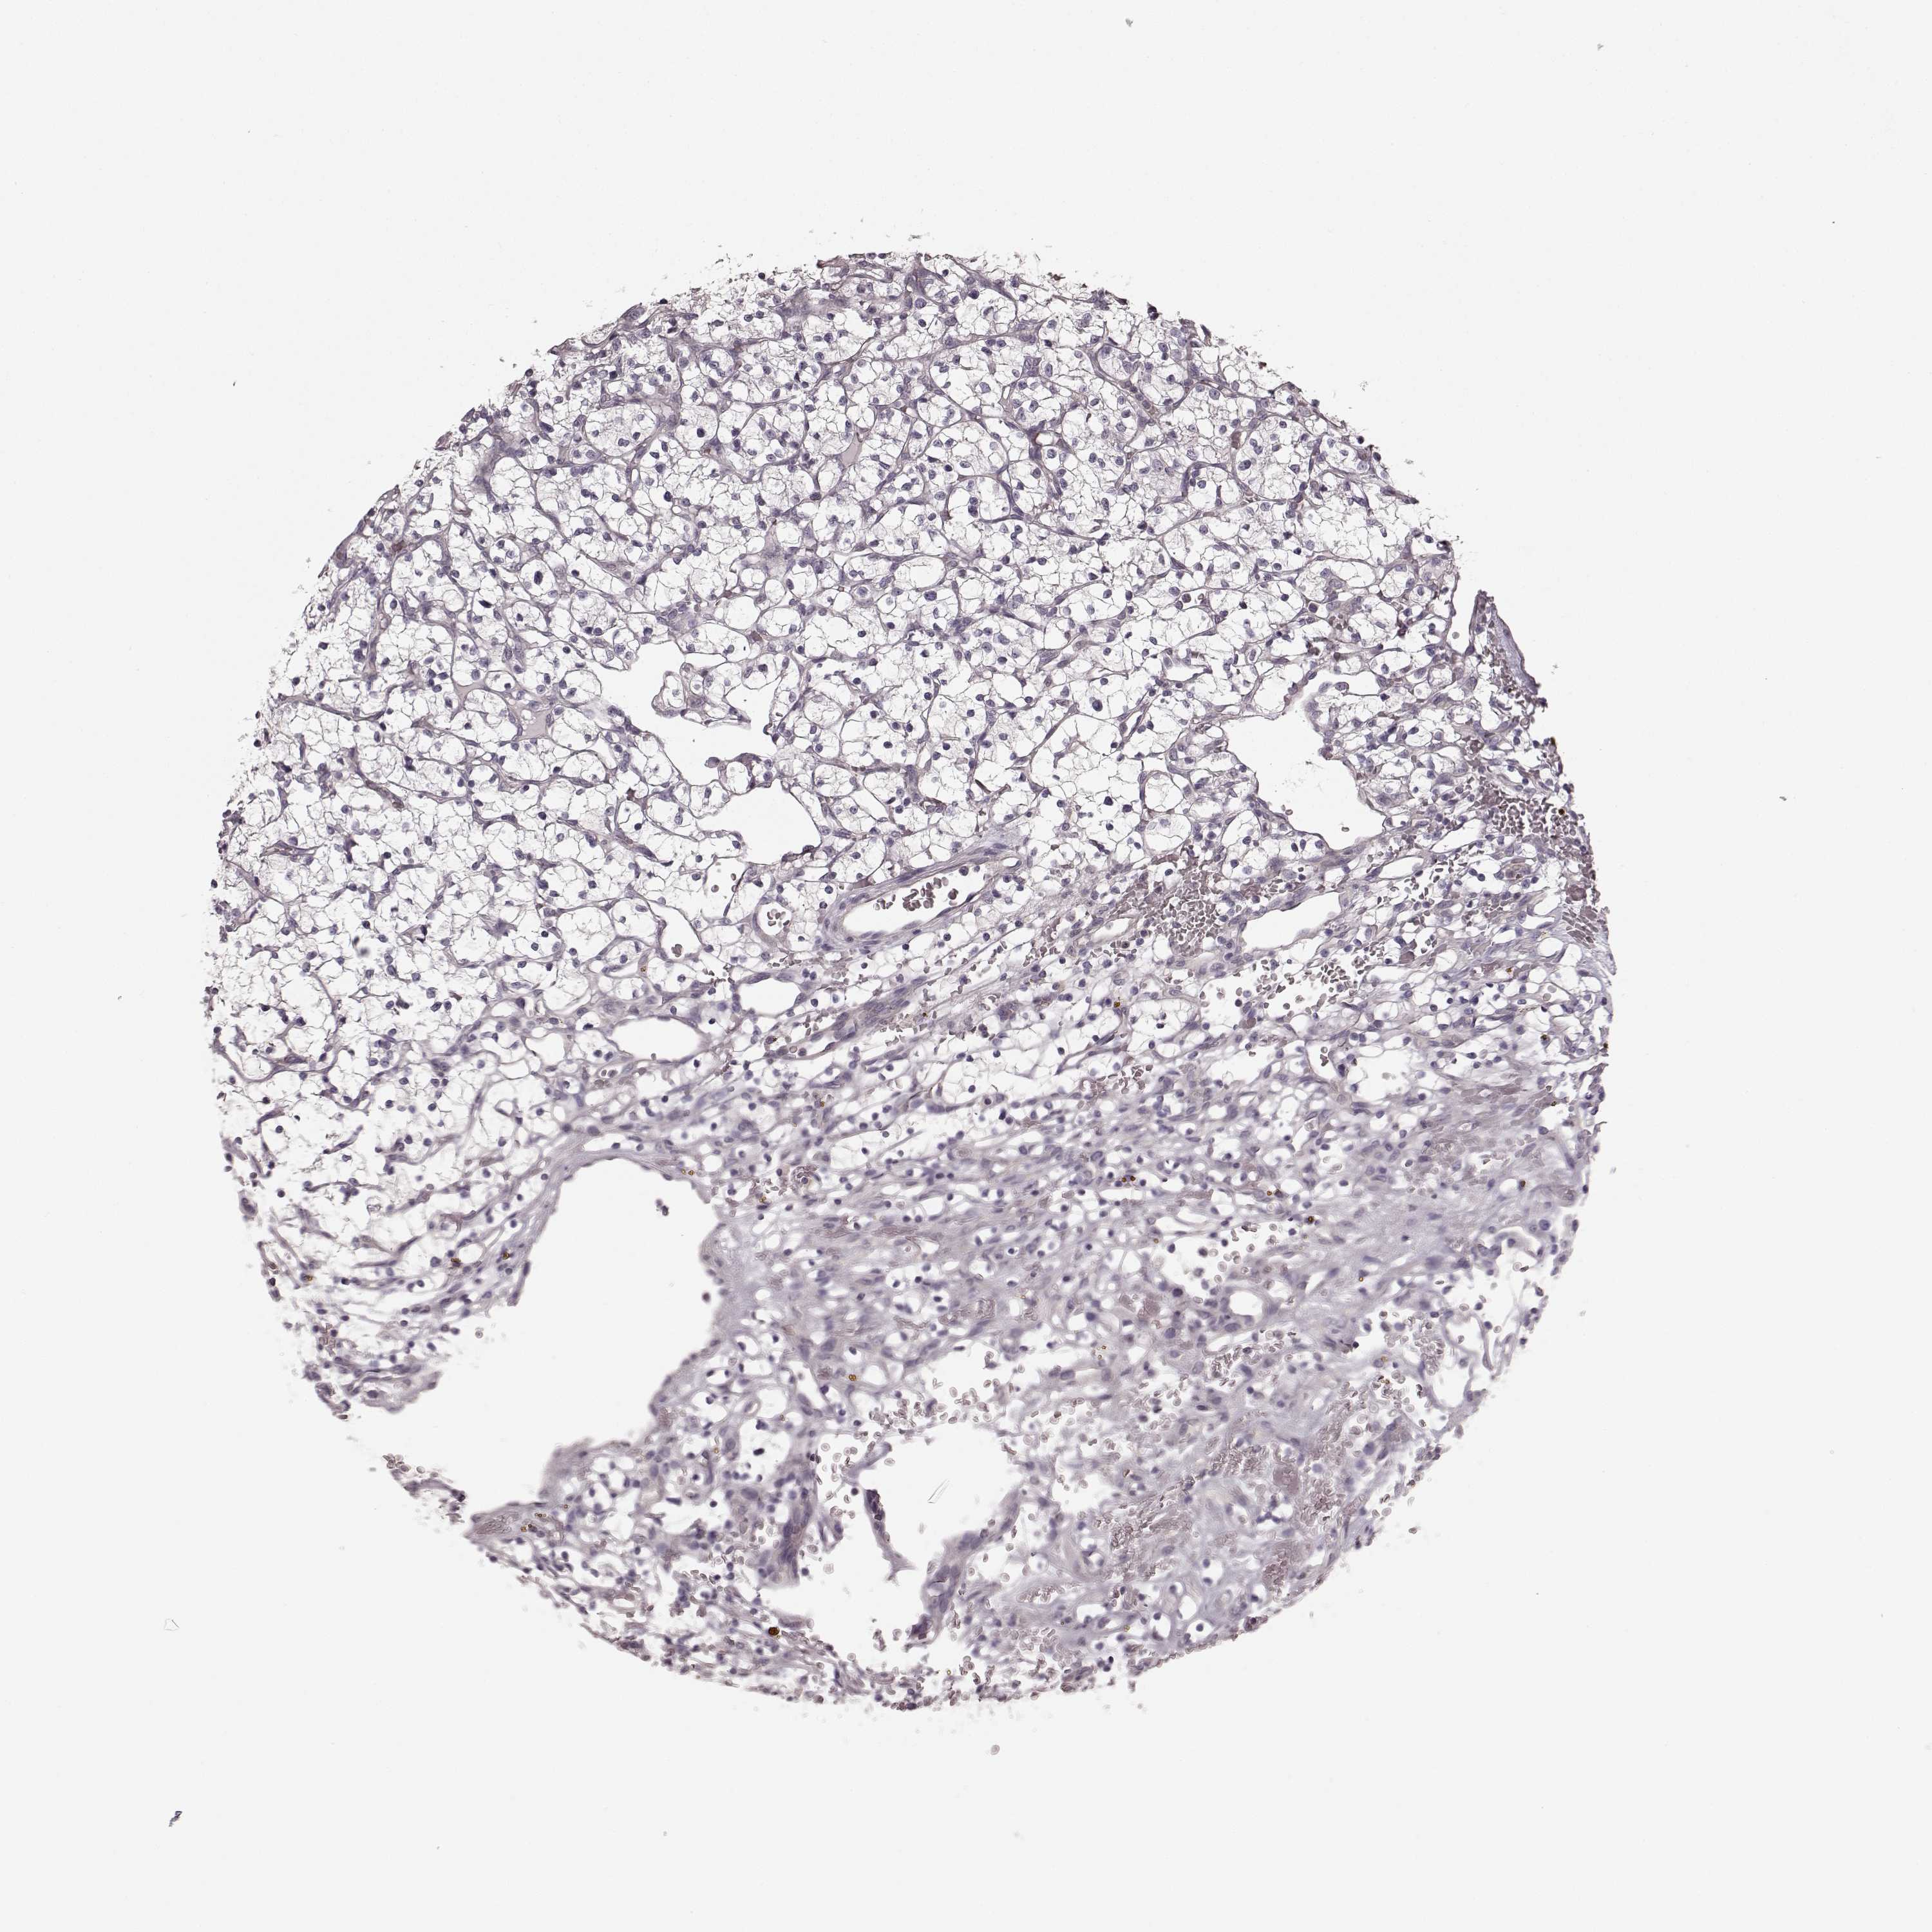

CANCER RENAL CANCER Show tissue menu

KICH TCGA KIRC TCGA KIRC VALIDATION KIRP TCGA PROTEIN RCC CPTAC PROTEIN EXPRESSION

KIDNEY CHROMOPHOBE (TCGA) - Interactive survival scatter ploti

The Survival Scatter plot shows the clinical status (i.e. dead or alive) for all individuals in the patient cohort, based on the same data that underlies the corresponding Kaplan-Meier plots. Patients that are alive at last time for follow-up are shown in blue and patients who have died during the study are shown in red.

The x-axis shows the expression levels (FPKM) of the investigated gene in the tumor tissue at the time of diagnosis. The y-axis shows the follow-up time after diagnosis (years). Both axes are complimented with kernel density curves demonstrating the data density over the axes. The top density plot shows the expression levels (FPKM) distribution among dead (red) and alive patients (blue). The right density plot shows the data density of the survived years of dead patients with high and low expression levels respectively, stratified using the cutoff indicated by the vertical dashed line through the Survival Scatter plot. This cutoff is automatically defined based on the FPKM cutoff that minimizes the p-score. The cutoff can be changed by dragging the vertical line or by entering a cutoff value in the square labeled "Current cut-off".

Under the Survival Scatter plot the p-score landscape (black curve; left axis) is shown together with dead median separation (red curve; right axis). Dead median separation is the difference in median mRNA expression between patients who have died with high and low expression, respectively. It is calculated as follows: median FPKM expression of dead patients with high expression - median FPKM expression of dead patients with low expression. This is intended to aid the user in visually exploring custom cutoffs and the associated p-scores and dead median separation.

Individual patient data is displayed and can be filtered by clicking on one or more of the category buttons on the top of the page. Categories describing expression level and patient information include: high, low, alive, dead, female, male and tumor stages. The scale of the x-axis can be toggled between linear and log-scale by clicking on the "x log" button. Mouse-over function shows TCGA ID, patient information and mRNA expression (FPKM) for each patient.

& Survival analysisi

Kaplan-Meier plots summarize results from analysis of correlation between mRNA expression level and patient survival. Patients were divided based on level of expression into one of the two groups "low" (under cut off) or "high" (over cut off). X-axis shows time for survival (years) and y-axis shows the probability of survival, where 1.0 corresponds to 100 percent.

PRKCE is not prognostic in Kidney Chromophobe (TCGA)